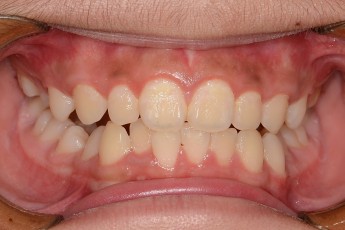

Before

After